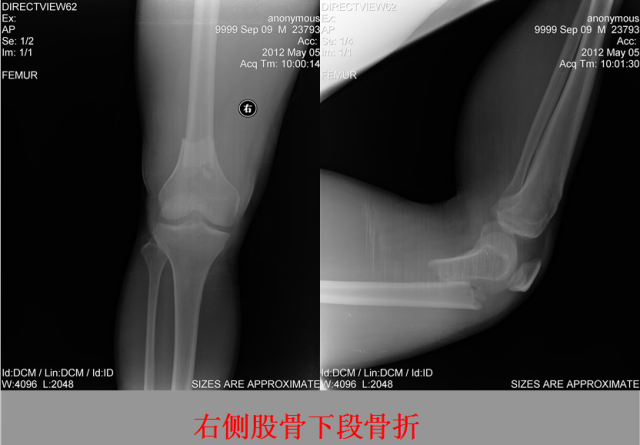

骨折篇

01

定义:骨折{Fracture}是指骨的完整性和连续性的折裂或粉碎。包括创伤性骨折、疲劳性骨折和病例理性骨折。 临床上以创伤性骨折*常见。